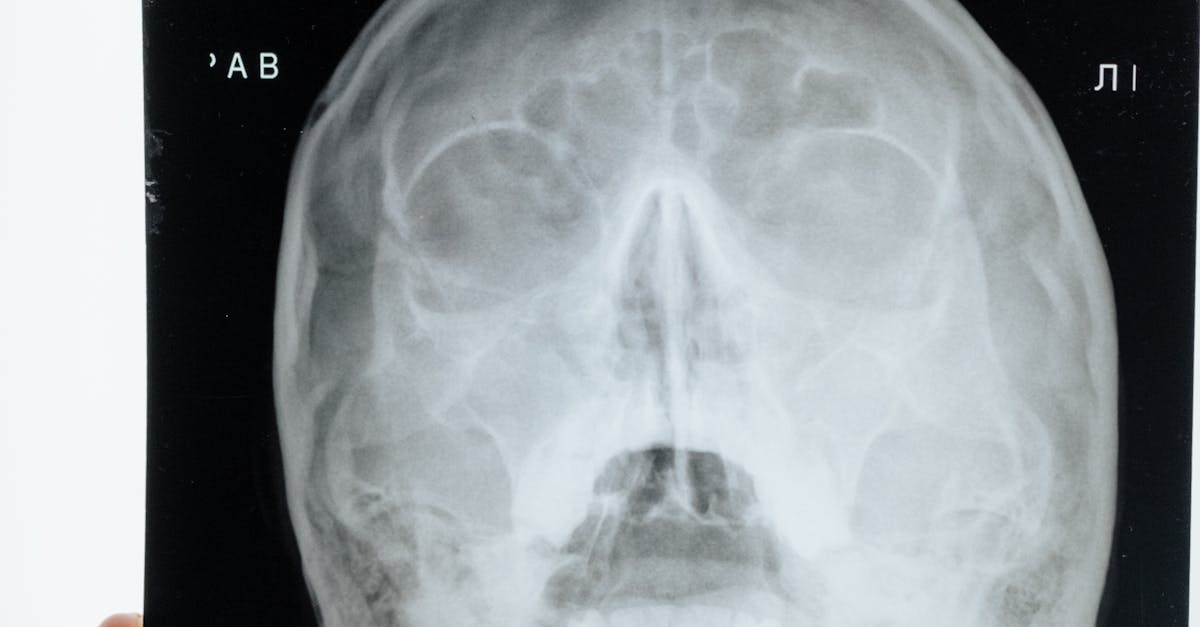

Non-invasive diagnostic procedures are valuable tools in the medical field for assessing various health conditions without the need for surgery or other invasive methods. These procedures utilize advanced imaging technologies such as MRI, CT scans, ultrasounds, and X-rays to provide detailed images of internal organs and tissues, allowing healthcare providers to investigate potential abnormalities or monitor existing conditions. These imaging techniques are often preferred for their ability to provide valuable diagnostic information while minimizing patient discomfort and recovery time.

Another alternative to full body scans is a CT scan, which uses X-rays to create detailed cross-sectional images of the body. CT scans are particularly useful for detecting conditions such as cancer, heart disease, and internal injuries. Additionally, ultrasound imaging can be used as an alternative, especially for issues related to the abdomen, pelvis, or vascular system. Ultrasound is a safe and painless procedure that uses sound waves to create images of the body's internal structures.